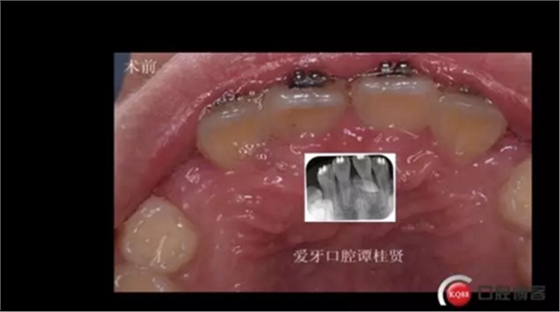

三年半前,家長(zhǎng)領(lǐng)著小孩前來(lái)要求矯正牙齒,男,約八歲,兩中切牙間隙約12MM,有一多生牙,全景片顯示深處還橫著一顆,也許正處叛逆期,小孩非常的調(diào)皮,經(jīng)過(guò)幾次的各種哄和商談,也可能為了好看,終于勉強(qiáng)同意先拔掉露出的多生牙,前牙片斷弓關(guān)閉間隙

拔掉一顆后大概大半年時(shí)間很快就把間隙關(guān)閉了,但是由于還有一顆橫在兩中切牙間,牙縫始終得不到完全關(guān)閉,此時(shí)只能拔掉深部埋伏阻生的牙才能進(jìn)一步矯正治療,但小孩一聽(tīng)又要做一次手術(shù)有不同意了,這樣又拖了兩年多,長(zhǎng)大了一些自然懂事了些。